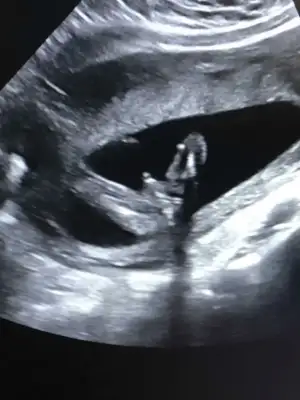

Çok uzun olmuş ama benim ki ne ozaman

• 1187FF75-2710-4BB2-B13D-E1BCAE348F99.webp

1187FF75-2710-4BB2-B13D-E1BCAE348F99.webp

24,5 KB · Görüntüleme: 278